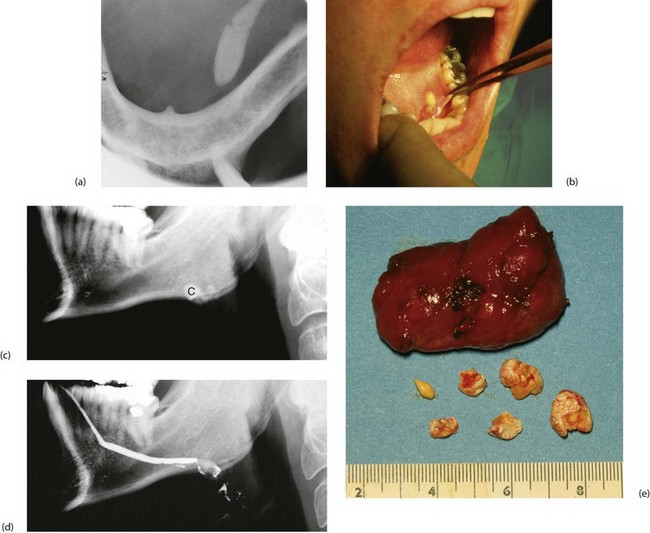

Submandibular stones may be found anywhere along Wharton's duct (Fig. 47.4), including its course within the gland. Stones vary from several millimetres to a centimetre in diameter. Those in the distal duct tend to have an elongated ‘date stone’ shape (see Fig. 47.5a).

Plain X-rays demonstrate most calculi. For the submandibular gland and duct, an occlusal film held between the teeth shows the floor of the mouth, and a lateral oblique gives a second viewpoint. For the parotid, AP and lateral views are often used. Contrast radiography of the ducts (sialography) is sometimes indicated if the history suggests stone disease yet no stone is palpable or visible on plain X-ray, although this has largely been replaced by ultrasound. Sialography (Fig. 47.7) requires cannulation of the salivary duct which may reveal a stenosis of the orifice and may relieve symptoms temporarily. Stenosis alone of any part of the duct may produce symptoms similar to calculus obstruction.

The anterior two-thirds of the submandibular duct lie in the floor of the mouth and calculi here are removed via an intraoral (Fig. 47.5a) approach. Immediately before operation, the stone should be confirmed to be present by palpation or X-ray. Operation may be performed under local or general anaesthesia. A longitudinal incision is made in the duct over the stone and the stone lifted out. If the stone is impalpable, the duct is incised from the orifice backwards and the stone removed with forceps. The incision is not sutured but left open to improve salivary drainage. Stones can also be removed endoscopically or destroyed by lithotripsy.

Less commonly, calculi lie within the gland where they are often multiple (Fig. 47.5c–e). The usual treatment is to excise the entire submandibular gland via an incision below the mandible, placed to avoid damaging the mandibular branch of the facial and avoiding the hypoglossal nerve.